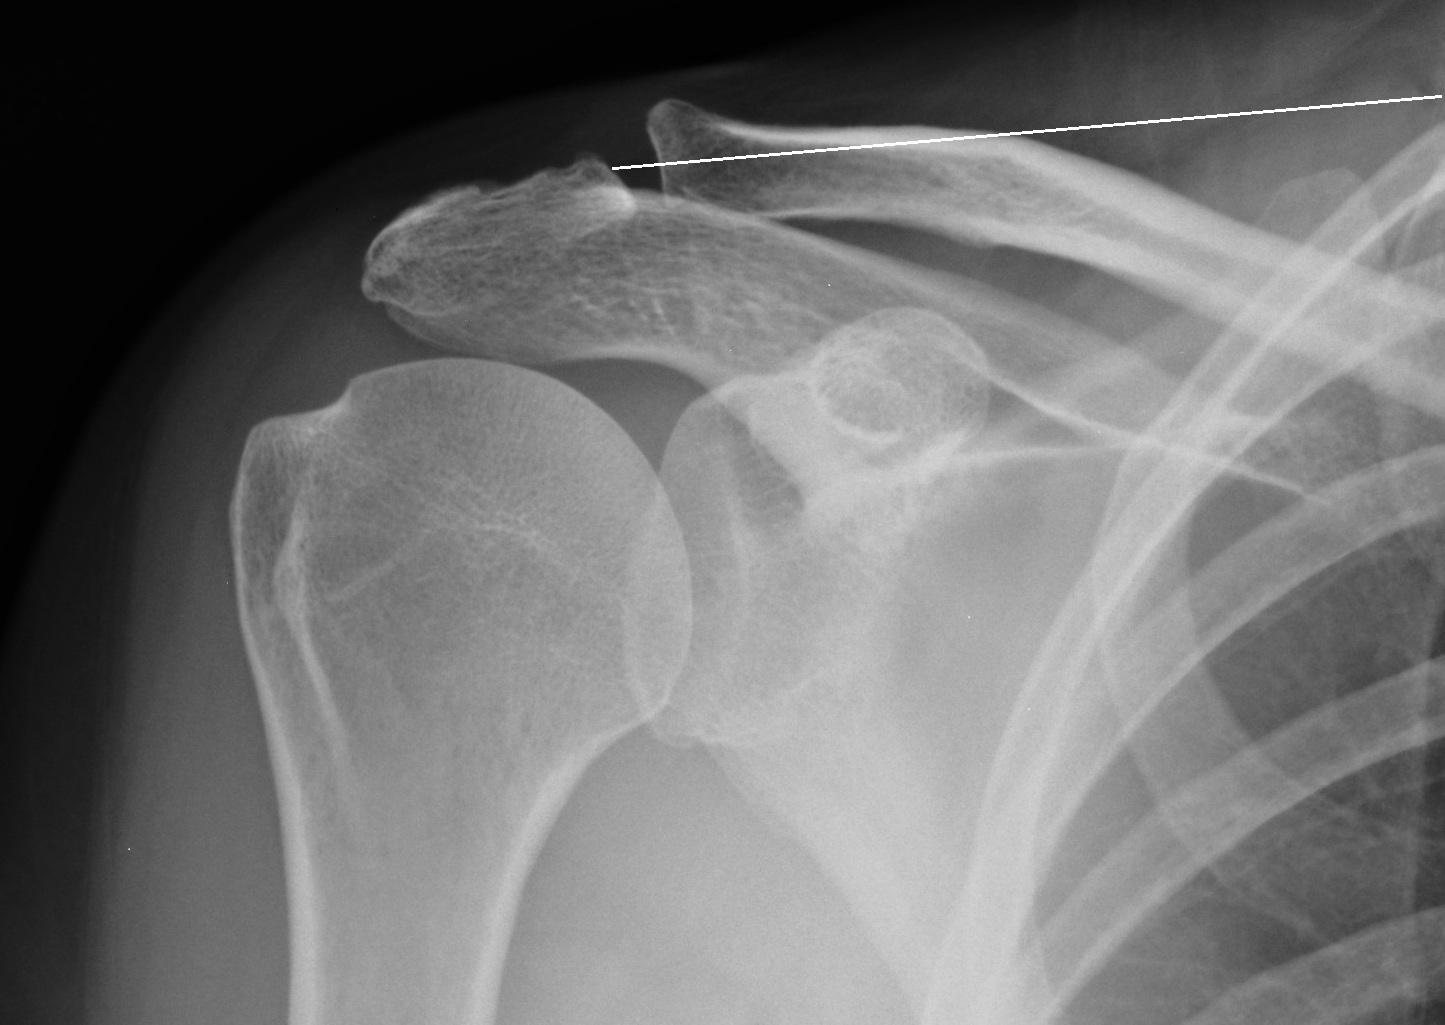

X-ray of Arthritic Acromioclavicular  Joint

Sometimes (normally from overuse) the joint between the acromion and collarbone can become arthritic.

X rays and an ultrasound or MRI scan.